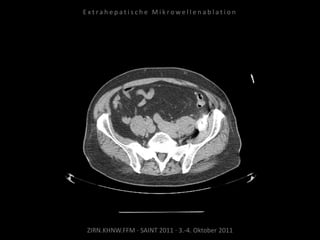

Erneute Ablation der Metastase

kaudal der linken Niere am

09.05.2011:

2 Nadelpositionen.

Verlaufskontrolle:

MRT 09.06.2011

MRT 10.08.2011

CT 15.08.2011

Keine weitere Tumorvitalität.